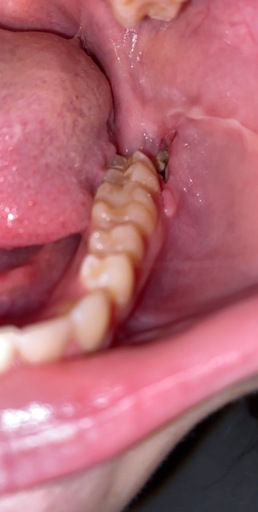

Gums where wisdom teeth were removed after 2 years seem to be suddenly opening again.

I had my wisdom teeth out almost 2 years aago. And just earlier I had noticed that I tasted slight blood in my mouth. I came to realize that where I had my wisdom teeth removed it seemed like it was starting to open back up again. It's slightly swollen and sore and it stings. Cannot get picture with where it is at

It is very unusual that the extraction sites would reopen after so many years. If this is only happening in one area, it may be a sign of a periodontal issue or it could be an issue with the tooth next to the extraction site. Bleeding in the mouth if not from trauma is usually an indication that there is an infection or disease present and should not be ignored. Schedule an appointment with your general dentist immediately or you can schedule a follow-up with the oral surgeon that treated you 2 years ago.

You need to seek the advice of a dental professional, preferably a periodontist or oral surgeon, who does this kind of work, and have him or her take an X-ray, either a CT scan or Panorex. The image should be not only of your teeth but also your jawbone. This will allow you to rule out any kind of infection, cyst, or problem at the extraction site that could account for the recurring swelling. It's possible that there's a problem with the tooth adjacent to the extraction socket. The tooth might have a cavity or need a root canal treatment, which would makes it feel as though it's affecting the socket area.